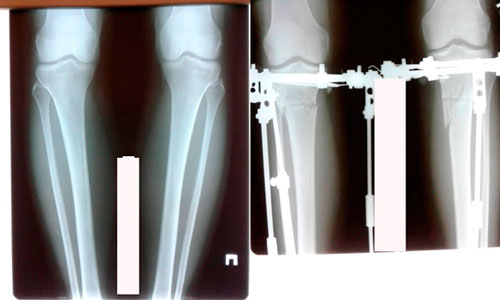

Исходник - 42 года.

Дата операции - 04.06.2020

image-04-06-20-04-35-1.jpg

image-04-06-20-04-35-8.jpg